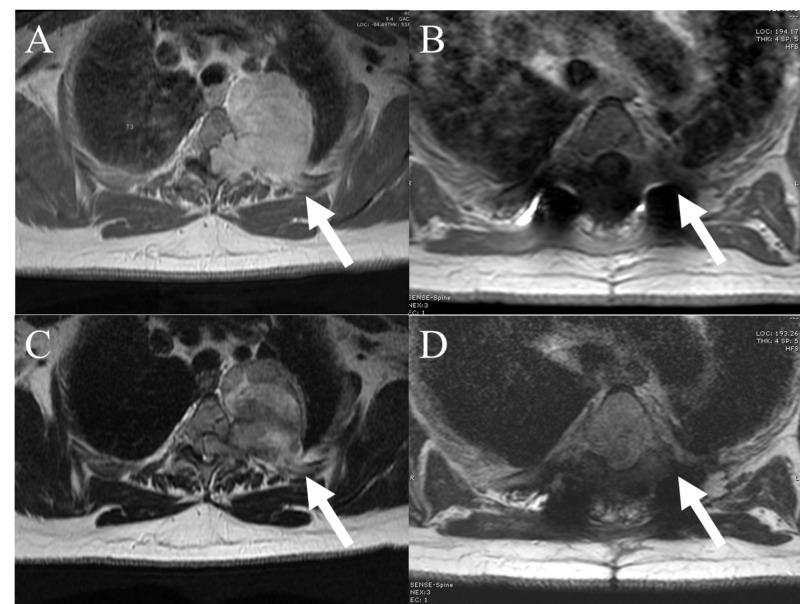

Dumbbell spinal cord tumors are infrequent pathologic entities. The optimal approach to safe surgical resection is ill-defined and must often be individualized. This is assisted with multiple tumor classification systems. Here, we describe a novel technique used to safely and successfully resect a large thoracic dumbbell schwannoma originating from the left T3 spinal nerve root with extension into the posterior mediastinum adjacent to the parietal pleura and thoracic aorta. A review of the literature was performed to study described surgical approaches to primary spinal dumbbell tumors. The decision-making process and preoperative imaging for operative planning are included. A detailed description of the procedure follows with intraoperative images. Gross total resection with no neurologic sequelae was achieved. Previously described operative techniques for resection of primary spinal dumbbell tumors with advantages and limitations of each are then reviewed. Gross total resection was safely achieved utilizing a single-staged posterior retropleural approach with anterior thoracoscopic guidance. The tumor was removed en bloc through a large posterior window. The prone position was utilized for the entire case with no intraoperative repositioning required. No intraoperative or immediate postoperative complications occurred. We report a novel approach to resecting a large primary spinal dumbbell tumor. A single-stage retropleural approach with anterior thoracoscopic guidance facilitated safe and successful gross total resection. Maintenance of the prone position throughout surgery allowed for reduced operative time, excellent anterior, and posterior visualization and no added patient morbidity. Repositioning to the lateral decubitus position may not be required in select cases.